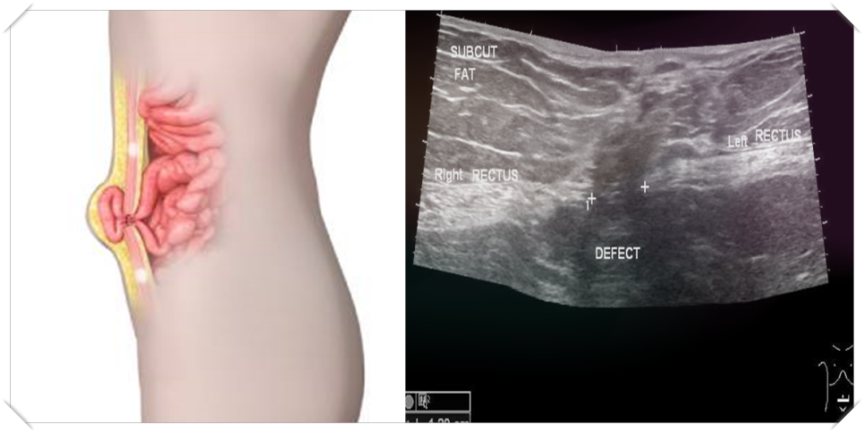

대개 허벅지 안쪽 골을 사타쿠니라고 해요. 이는 해부학적으로 ‘서혜부’라고 불리고 있습니다.서혜부 탈출증은 좌우 허벅지 안쪽 부분에 장이나 난소, 내장 지방 등이 뱃속에서 피부 바로 뒤까지 튀어나와 버리는 병이라고 할 수 있습니다. 이러한 탈증은 흔한 사타구니 통증의 원인인데 그 종류로는 바깥쪽과 안쪽과 대퇴부의 탈장이라는 3종류가 있으며, 부위에 따라 명칭이 다른 이유는 각각의 내장과 조직의 태도가 다르기 때문입니다.

서혜부탈장의 증상은 서혜부에 덩어리처럼 부드러운 팽창이 나타나며 시간이 지남에 따라 점차 커지는 특성이 있습니다. 기본적으로 선 상태에서 배에 힘을 주면 부풀어 오르는 증상이 커지고, 눕거나 손으로 밀어내면 부은 것이 들어가게 됩니다.

디스크 진단은 비교적 간단하게 알 수 있지만벽을 뚫고 창자가 탈출해 그 부위가 부풀어올라 일상생활에서 샤워를 하거나 옷을 입거나 누워있을 때 부풀어 있는 부분을 쉽게 확인할 수 있을 것입니다. 또한 튀어나온 것은 합병증을 동반하기 전까지는 누르면 들어가게 되는 것입니다.